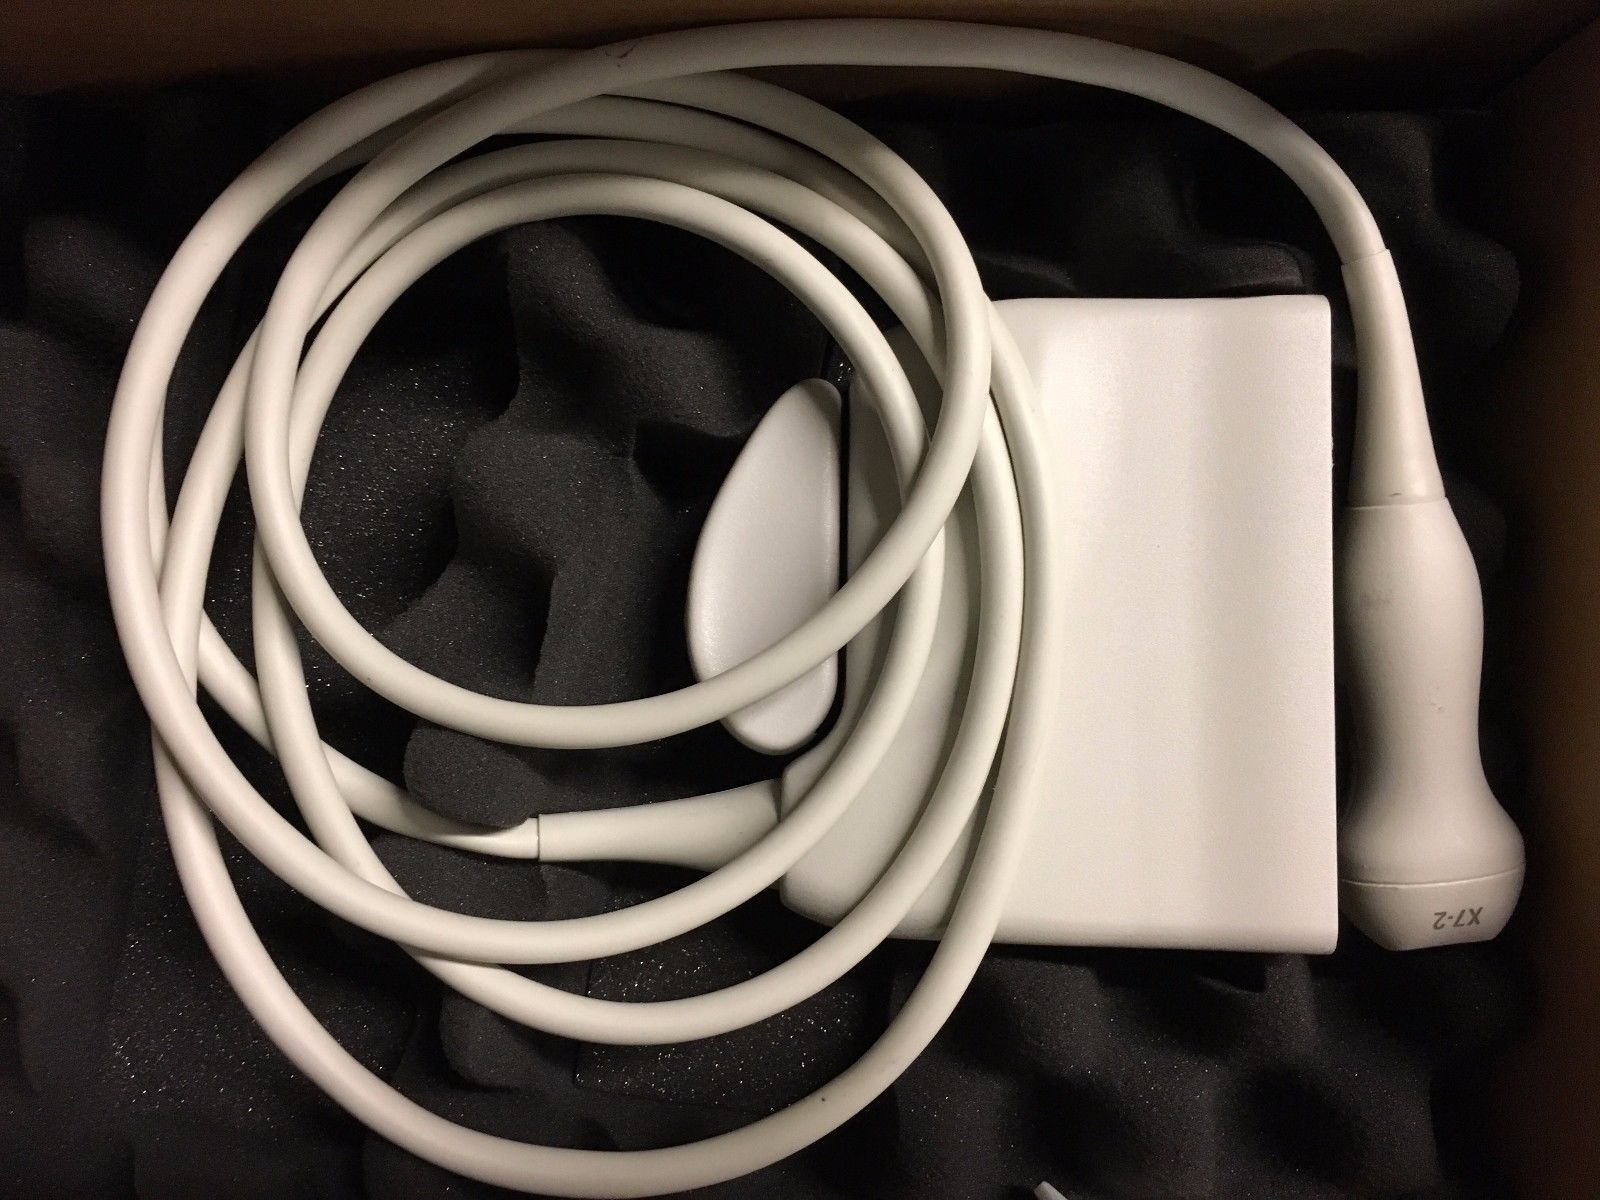

Philips Probes

DIAGNOSTIC ULTRASOUND MACHINES FOR SALE